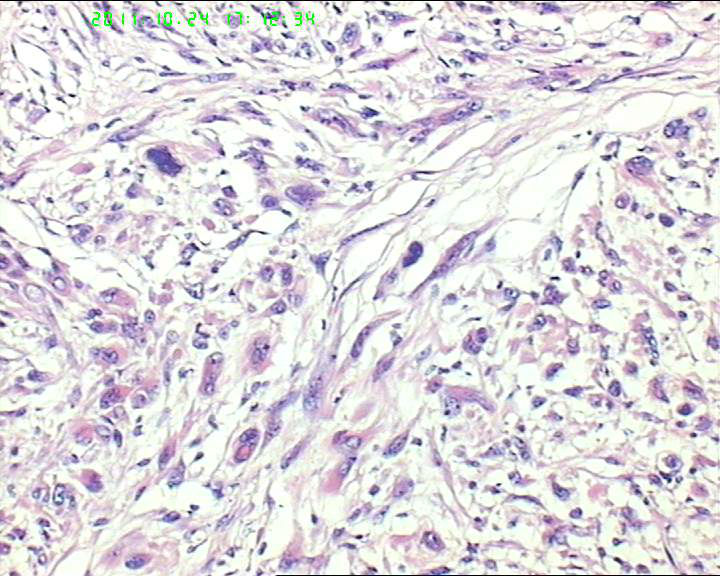

50岁女性腹膜后肿物,肉瘤?

灰红肿物一个,大小6.5*3.5*3cm。包膜完整,切面灰白实性质韧。

梭形细胞,异型性明显,可见多核巨细胞,胞质红染,似有横纹肌样分化,部分细胞可见胞质粘液,有核内假包涵体,所给的图像分裂相很少,结合大体,考虑低度恶性肿瘤。

1 平滑肌肉瘤

2高分化脂肪肉瘤(是否有横纹肌分化,要看免疫组化标记)

3恶纤组

梭形细胞肉瘤,倾向横向纹肌肉瘤,有些区域有席纹状结构,还需与恶纤组鉴别。

梭形细胞肉瘤:横纹肌肉瘤,平滑肌肉瘤,恶性间质瘤。倾向前者

梭形细胞肉瘤:MPNST?肌源性?GIST?MFH?标记鉴别。